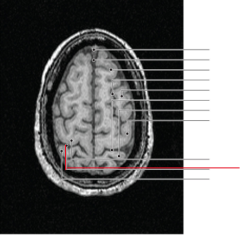

nucleus caudatus

putamen

globus pallidus

capsula interna (corona radiata)

hippocampus

laterale ventrikels (I en II)

septum pellucidum